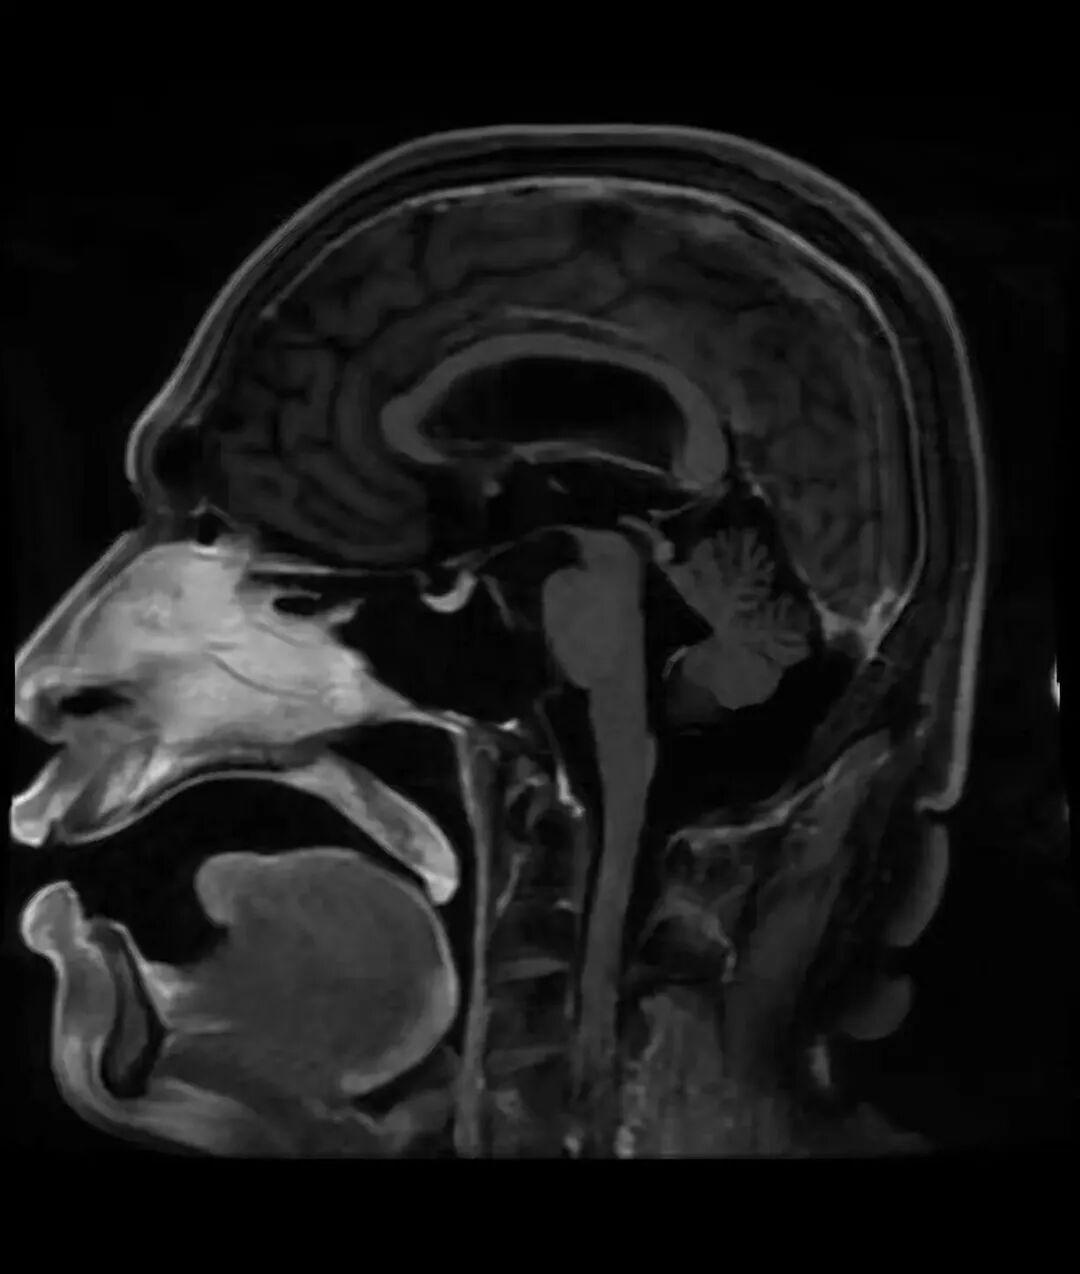

图:肺癌病例转变合并软脑膜转移

面对这样的绝境,高博医疗集团上海高博肿瘤医院的胸部肿瘤科李爽主任团队决定采用鞘内注射的治疗方法,即将药物直接注入脑脊髓液中,以控制颅内病灶。李爽主任向家属耐心解释:“肺癌如果出现软脑膜转移,颅内情况将是首要解决的主要矛盾。如果不及时控制,患者可能会出现癫痫、意识障碍,生存时间也会明显缩短。”在向家属详细解释了两种治疗方式——通过ommaya囊注射和传统腰穿注射的利弊后,考虑到手术风险和患者实际情况,家属选择了更为保守但同样有效的腰穿鞘内注射。